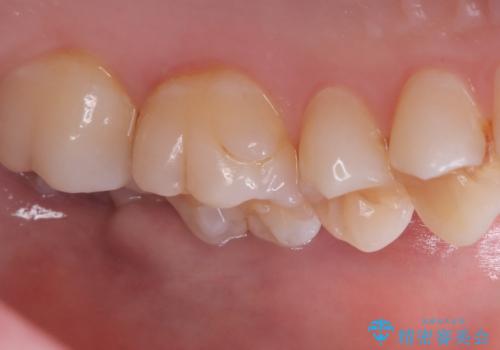

- 主訴:左上真ん中らへんの歯が欠けてしみるので治したい

審美性、適合性の良いセラミックインレーでのやり替えとなりました。

左上4近心に実質欠損を認め、遠心から咬合面にかけてはCR修復が施されていたため、MODインレー窩洞としました。

インレー接着操作時はラバーダム防湿を行っています。